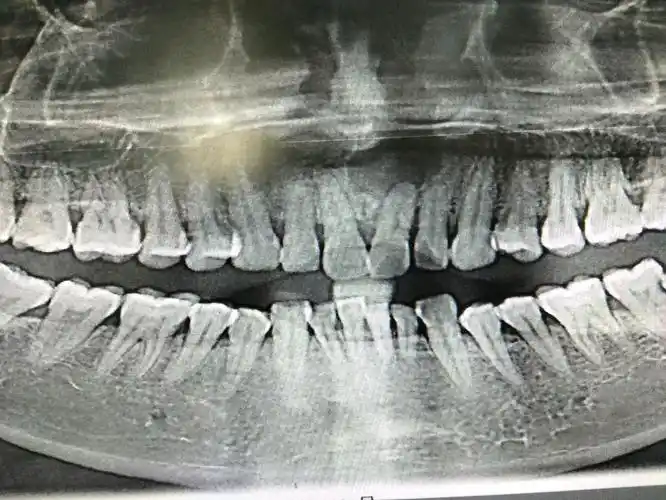

大牙牙龈下方长了个大包,不按不疼,大概两个月了,有的医生说是牙囊肿

记一次含牙囊肿手术

口腔cbct影像分析根尖囊肿的诊断